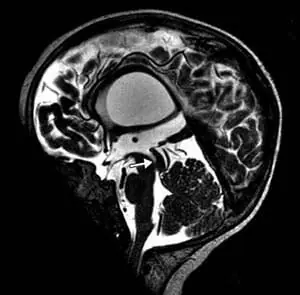

頭部磁気共鳴映像法では、テント上水頭症、視交叉陥凹のバルーニング、薄い脳梁、側脳室および第3脳室の拡張、透明中隔の欠如、および脳の低髄鞘化が明らかになった(図2)。

図2. 磁気共鳴画像法T2強調矢状画像。 脳梁は薄かった。 磁気共鳴画像法T2強調冠状断像。